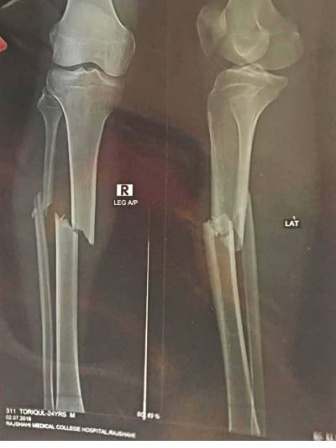

With two bones of his right leg broken, eight stitches on his head and bruises all over the body, Toriqul Islam still lies in his hospital bed.

Police and some journalists took him to Rajshahi Medical College Hospital where doctors plastered his broken leg up to his thigh. He has been kept under observation.

MAK Shamsuddin, head of orthopaedic surgery department of the hospital, said it would take at least three months for the broken bones to heal.

The X-ray plate shows both the bones of his right leg have been fractured.